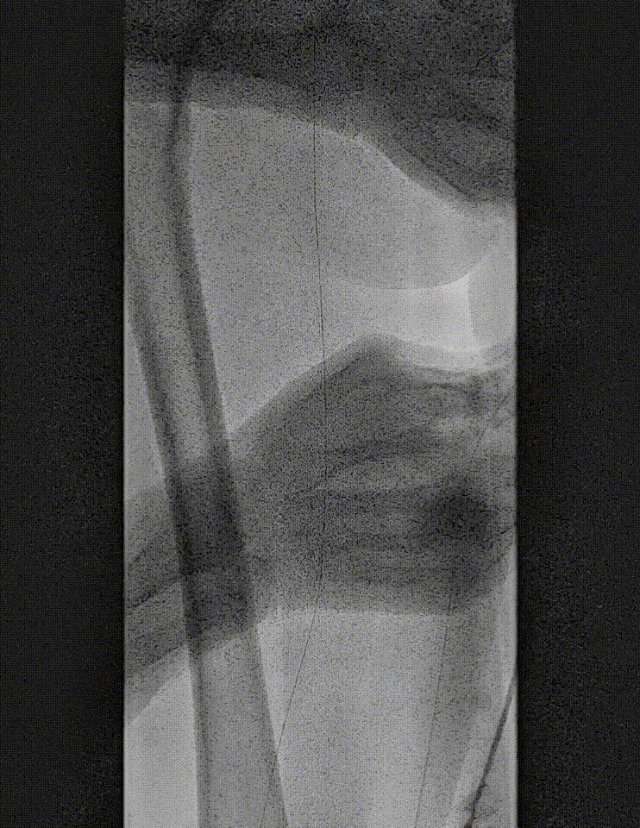

图:IN.PACT DCB 6-250 扩张,最终造影

图:DCB 5-250 扩张及全程造影

图:DCB扩张后 全程造影

图:DCB扩张后的全程造影